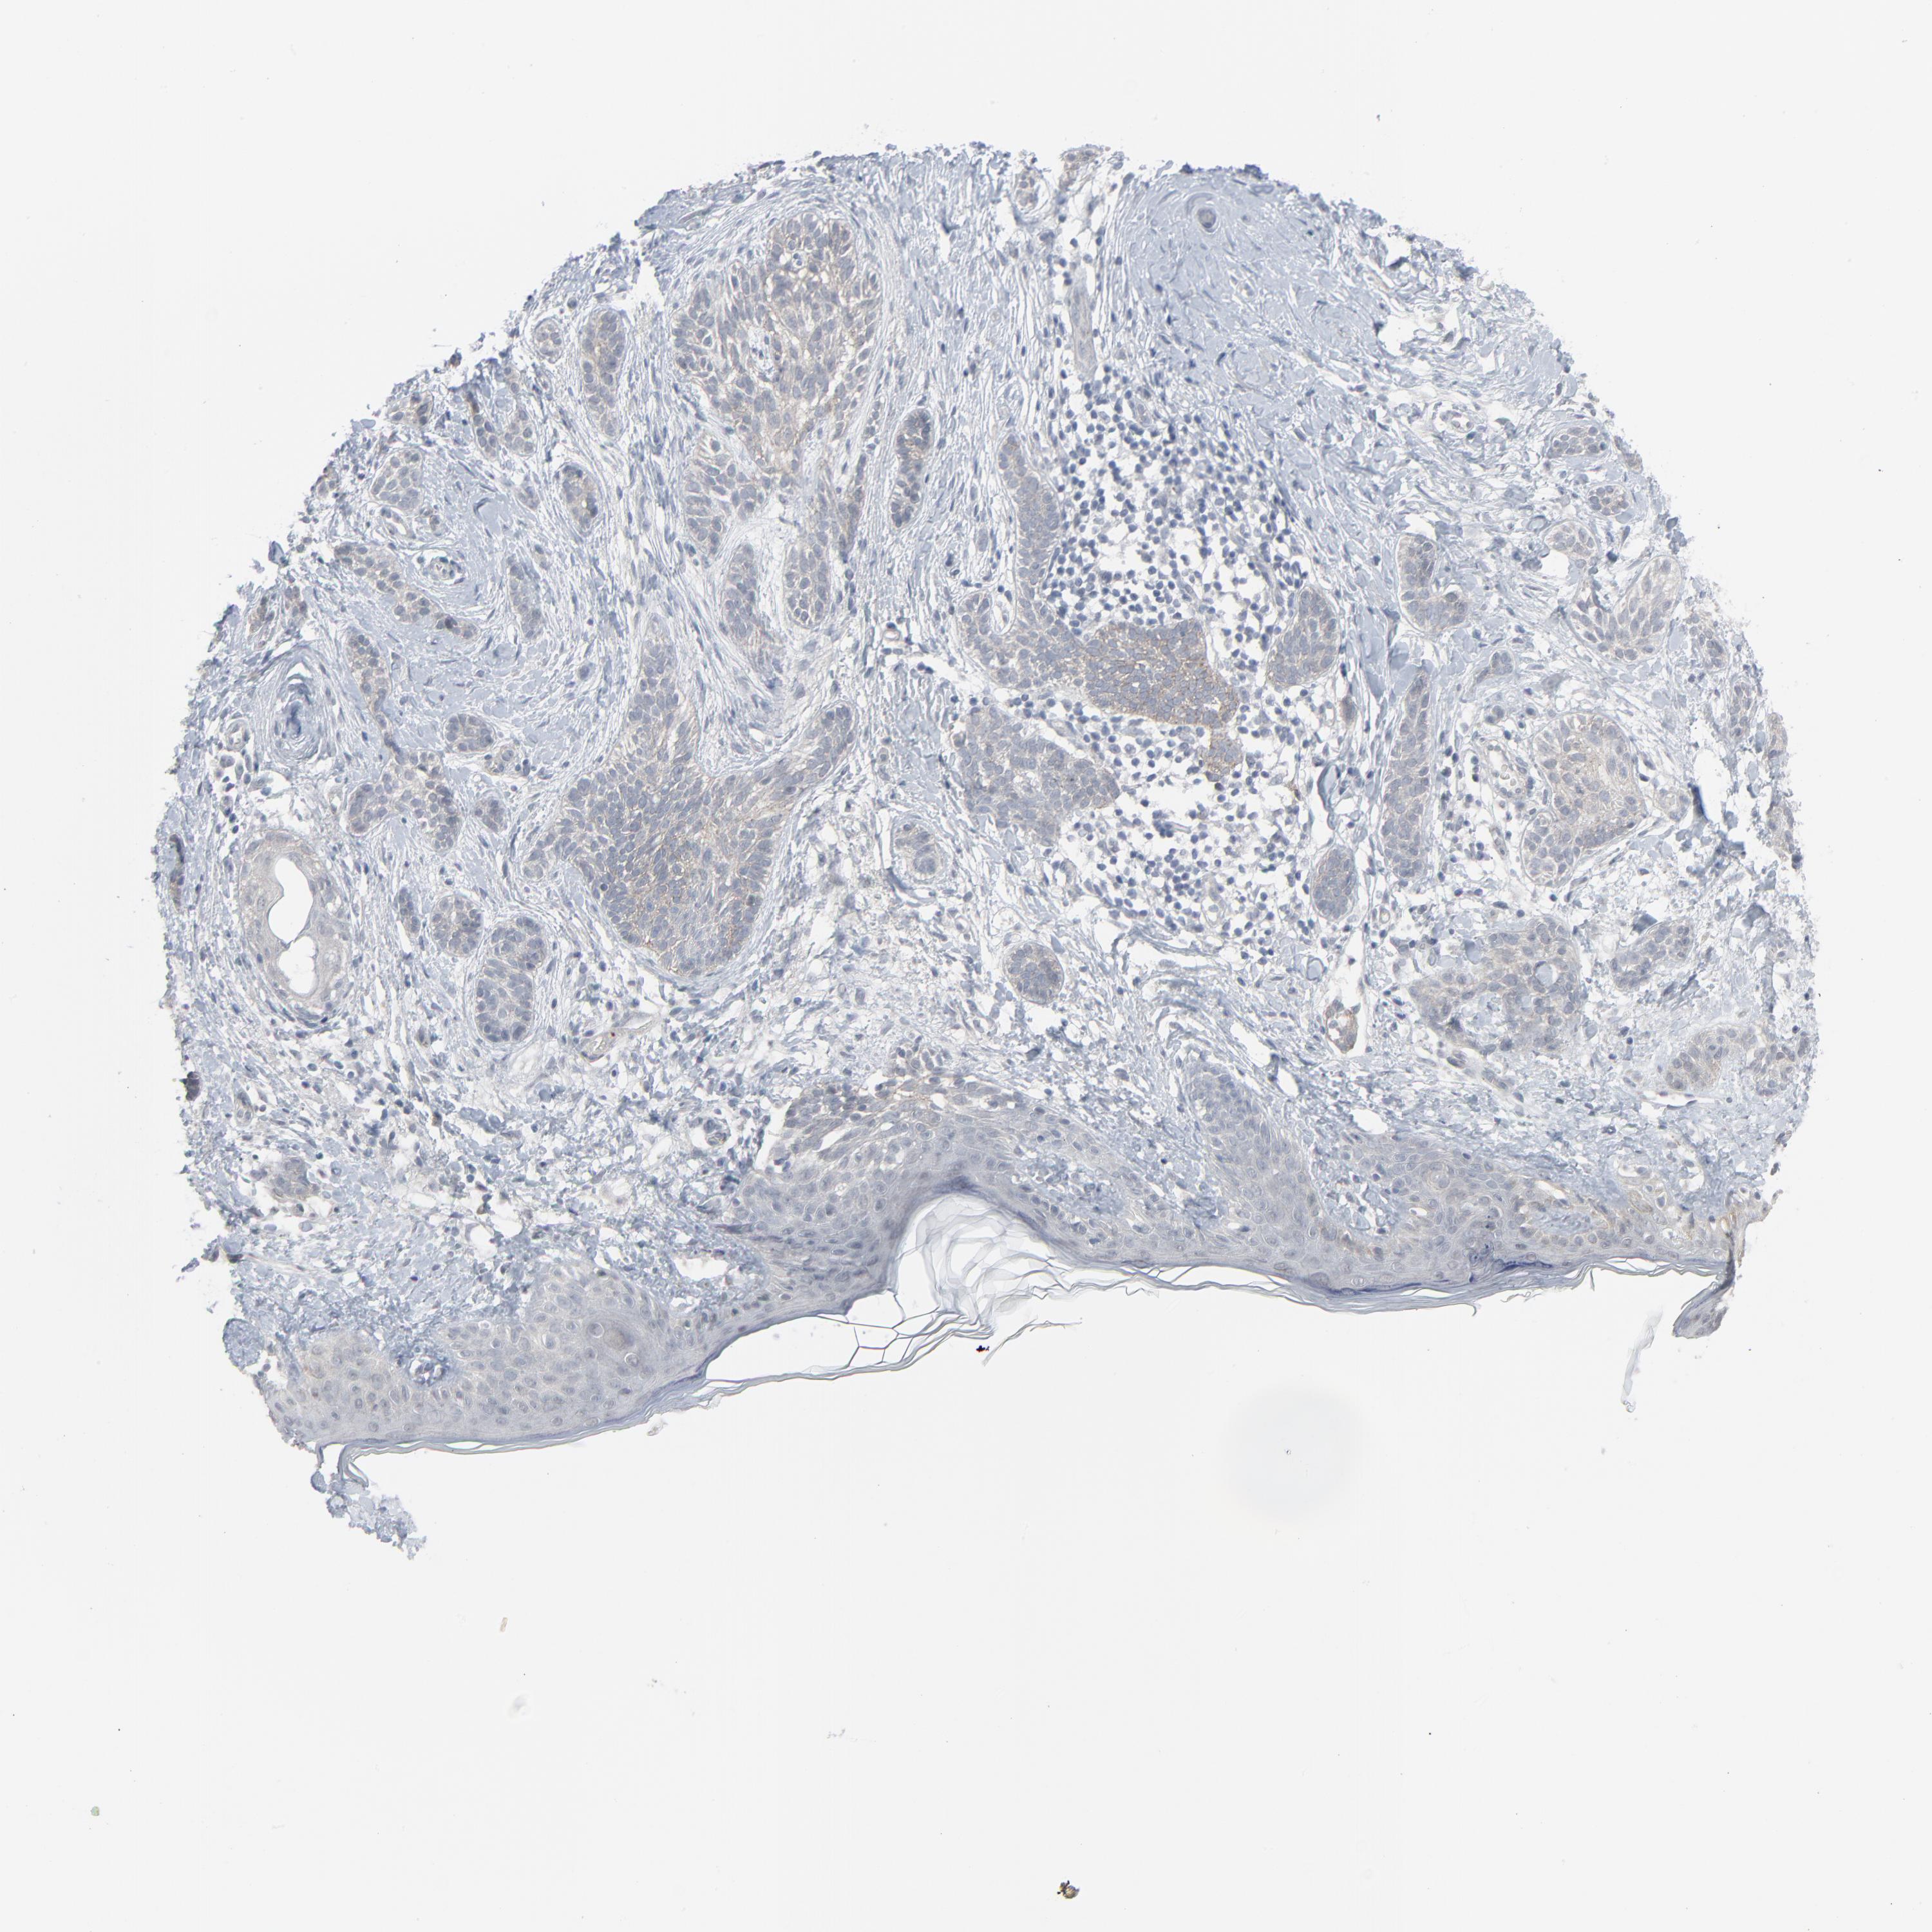

SKIN CANCER - Protein expressioni

A mouse-over function shows sample information and annotation data. Click on an image to view it in a full screen mode. Samples can be filtered based on level of antibody staining by selecting one or several of the following categories: high, medium, low and not detected. The assay and annotation is described here.

Antibody stainingi

Antibody staining in the annotated cell types in the current human tissue is reported as not detected, low, medium, or high, based on conventional immunohistochemistry profiling in selected tissues. This score is based on the combination of the staining intensity and fraction of stained cells.

Each image is clickable and will lead to virtual microscopy that enables deeper exploration of all samples and also displays staining intensity scores, fraction scores and subcellular localization as well as patient and tissue information for each sample.

Antibody HPA003278

Antibody CAB022450

Squamous cell carcinoma, NOS

Basal cell carcinoma